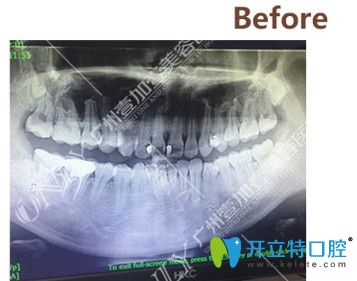

▼矯正前拍攝的CT

矯正前拍攝的CT

拍了CT之后,醫(yī)生根據我的情況給我進行了分析,我的情況還不算特別復雜,牙套可以選擇金屬的、半隱形的以及隱形的,問清楚了這幾種牙套的區(qū)別和價格之后,我選擇了價格中等,美觀度稍高的半隱形陶瓷牙套。